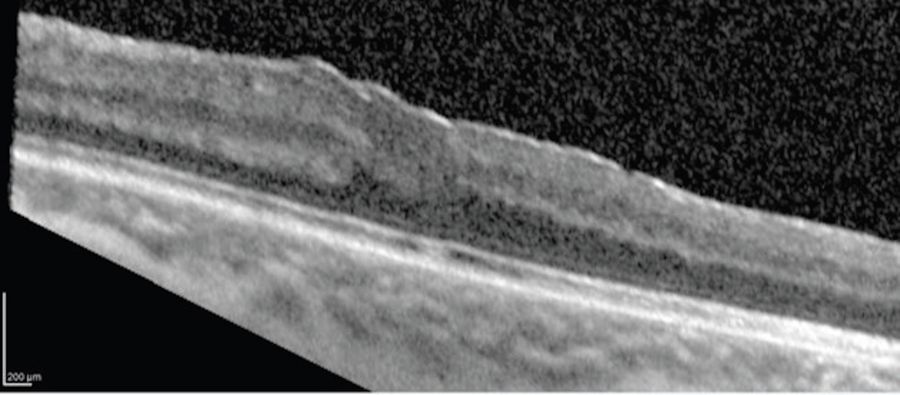

The hyaloid face was elevated by aspiration from the optic disc. The intraoperative OCT was helpful to see where the hyaloid was still attached during these maneuvers (Figure 2). In the case of split or tenacious hyaloid, triamcinolone stain can be helpful to visualize the vitreous both under the microscope and on the live intraoperative OCT images.

Intraoperative OCT provided valuable real-time insights on the configuration of the membrane, which can change after the hyaloid is lifted (Figure 3).